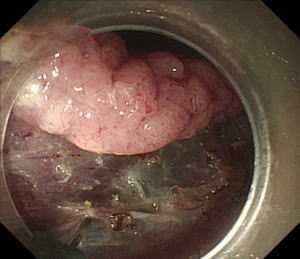

| 【大腸ESD】 |

直腸の半周近くを占める早期の直腸癌。癌の範囲をわかりやすくするためインジゴカルミンという青い色素を散布してあります。 |